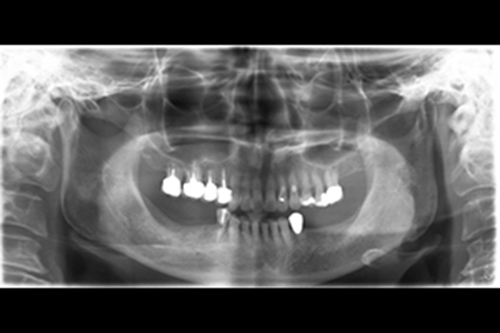

治療前全口x光片、口內照片